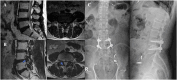

Results: There were significant improvements in visual analogue scale (VAS) and Oswestry Disability Index (ODI) scores after the operation in both groups. The FEL group tended to have significantly shorter hospital stay. Interestingly, a statistically significant increase in postoperative lumbar lordosis and segmental angle was observed in the FEL group and both groups, respectively. Spondylolisthesis was exacerbated or newly developed in five of the 21 patients (24%) in the STL group. In contrast, improvement in spondylolisthesis was observed in two of the 24 patients (8%) in the FEL group. There were no complications that resulted in fatal sequelae and no significant difference in the complication rate.

Conclusions: The clinical results of FEL were similar to those of STL. In addition, the results of FEL were superior to those of STL in terms of a decrease in the postoperative length of stay and radiologic instability, such as iatrogenic spondylolisthesis. The results of this study indicate that FEL is a comparable surgical method to STL for LSS.